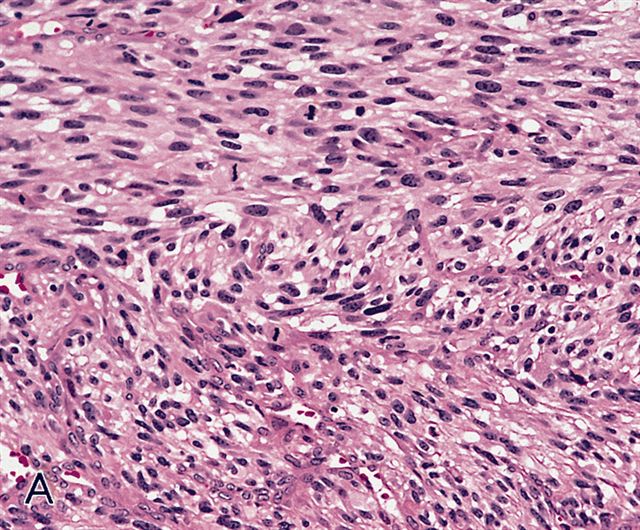

Microscopic (histologic) description

- Sheets of large, atypical and frequently multinucleated polygonal, spindled or rhabdoid eosinophilic cells (Am J Surg Pathol 2009;33:1850)

- Cross striations are seldom detected

Microscopic (histologic) images

Differential diagnosis

- Undifferentiated pleomorphic sarcoma: